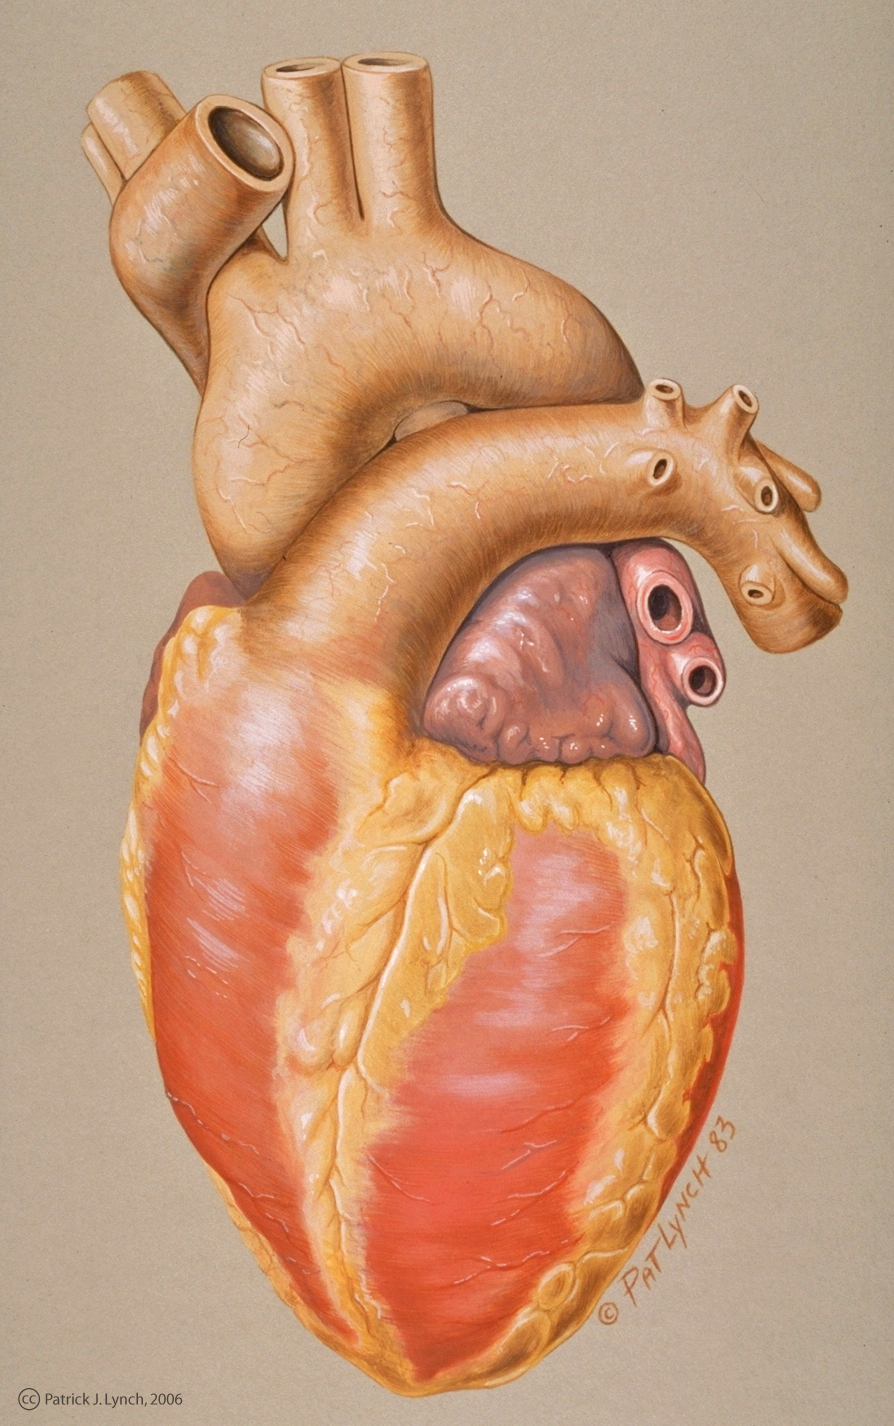

3d anatomy human heart  Show me a diagram of the human heart? Here are a bunch! - Interactive Biology, with Leslie Samuel

Show me a diagram of the human heart? Here are a bunch! - Interactive Biology, with Leslie Samuel  Real Human Heart Drawing at GetDrawings | Free download

3D Illustration Human Heart 3D Images - Iwish Iwas  Realistic Human Heart Drawing at GetDrawings | Free download

Realistic Human Heart Drawing at GetDrawings | Free download  Heart Anatomy Human Heart Images Hd 3D - Dreaming Arcadia

Heart Anatomy Human Heart Images Hd 3D - Dreaming Arcadia  Anatomical Heart Drawing at GetDrawings | Free download

How to Draw a Heart - Science Drawing Lesson | Heart drawing, Anatomical heart drawing, Human  Realistic Heart Drawing 1000 Ideas About Human Heart On Pinterest Anatomical Heart | Heart

Realistic Heart Drawing 1000 Ideas About Human Heart On Pinterest Anatomical Heart | Heart  Real Human Heart Drawing at GetDrawings | Free download

Real Human Heart Drawing at GetDrawings | Free download  Sketch Human Heart Diagram Labeled - fallinlovewithyou-raura